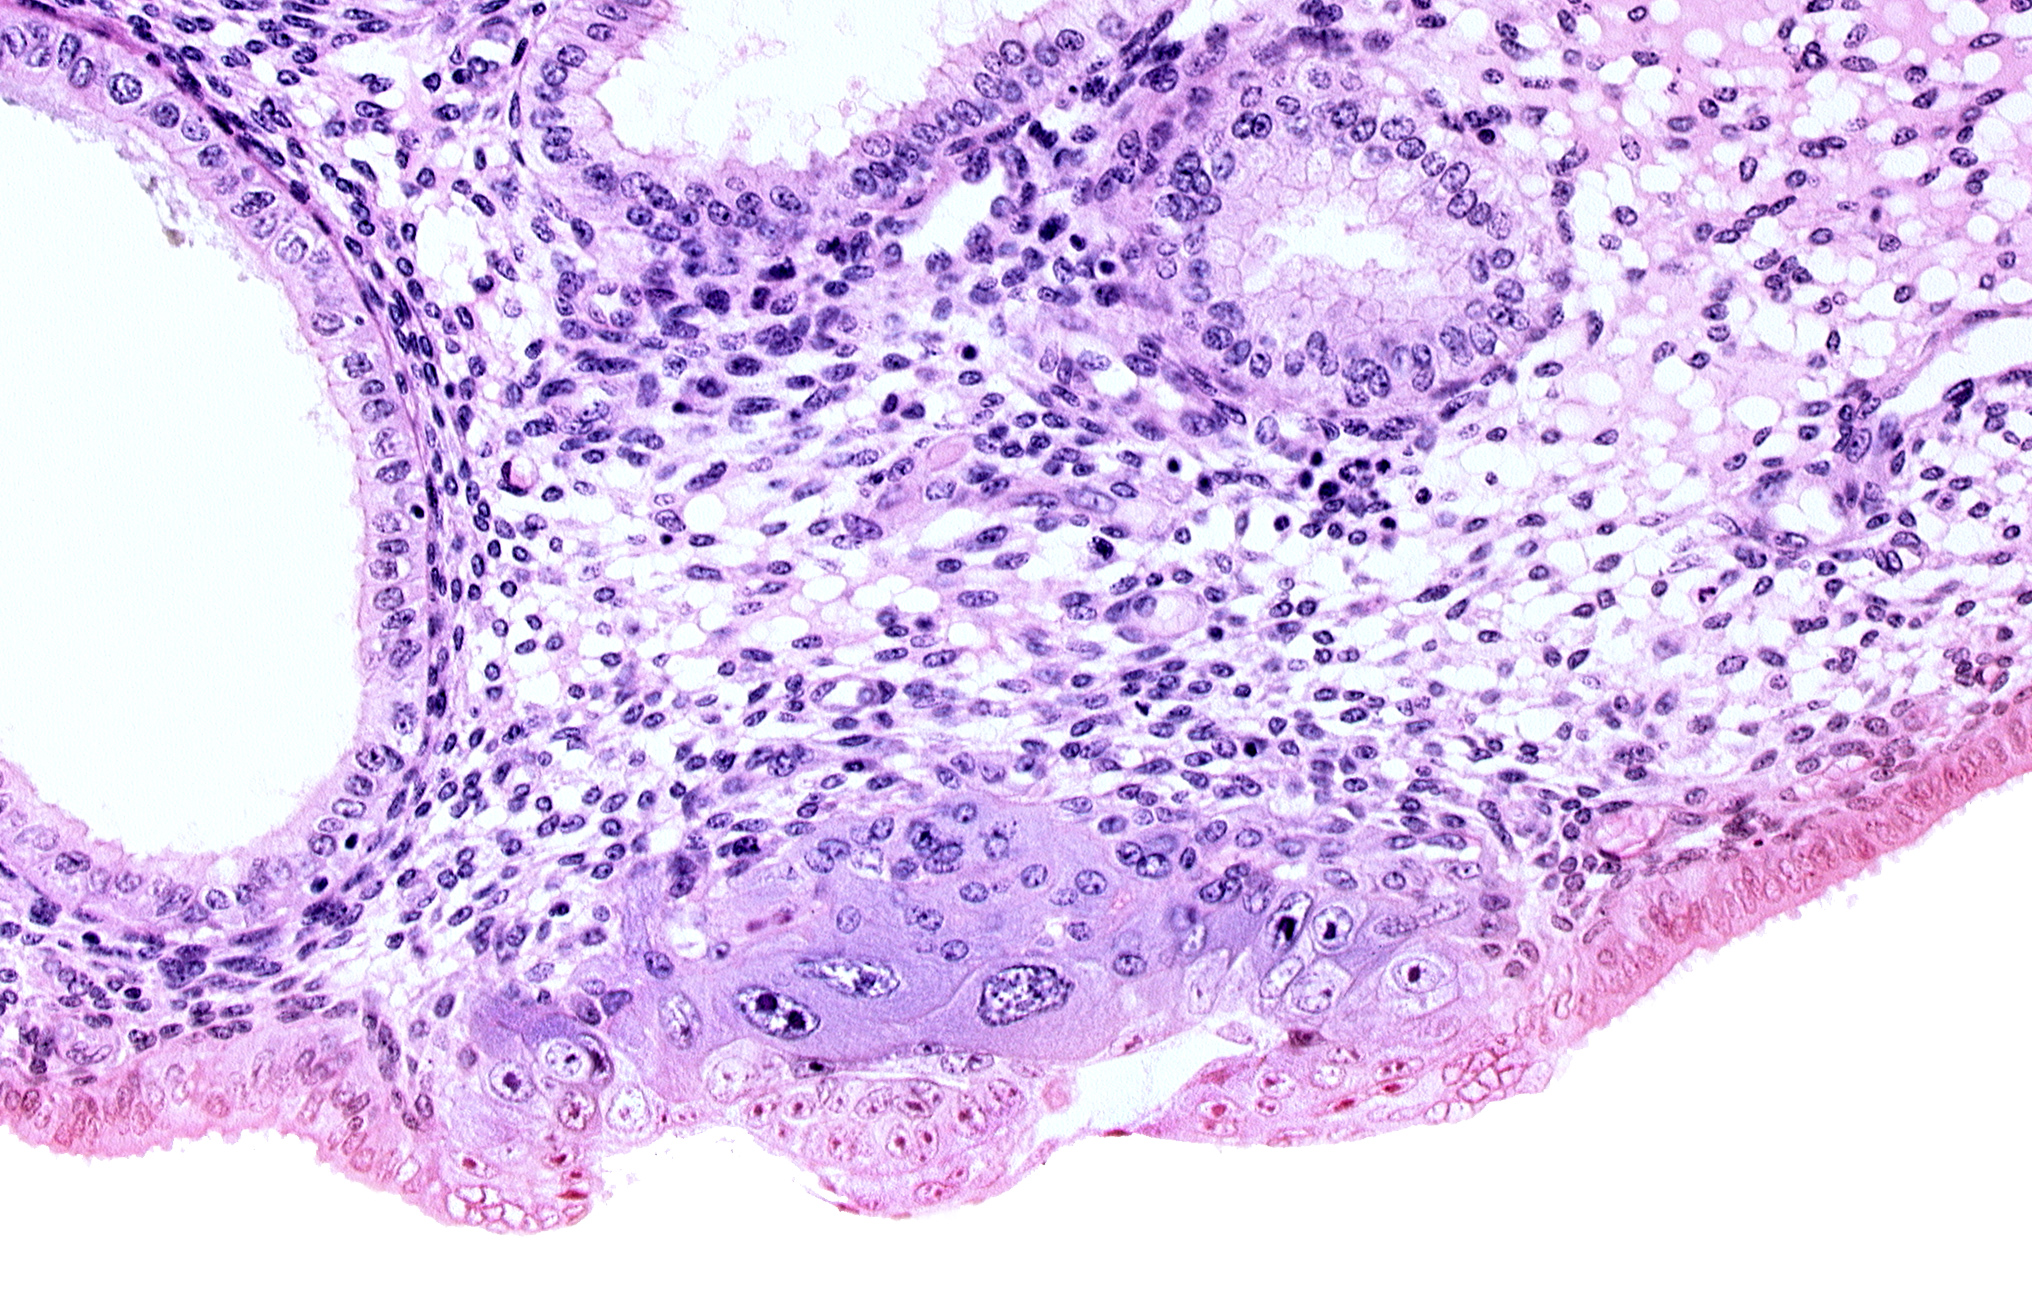

Carnegie Embryo #8020 | Location: 06-01-08

Keywords: amniotic cavity, blastocystic cavity (blastocoele), embryonic disc, endometrial sinusoid, membranous trophoblast at abembryonic pole, solid syncytiotrophoblast, syncytiotrophoblast / decidua interface

Source: The Virtual Human Embryo.